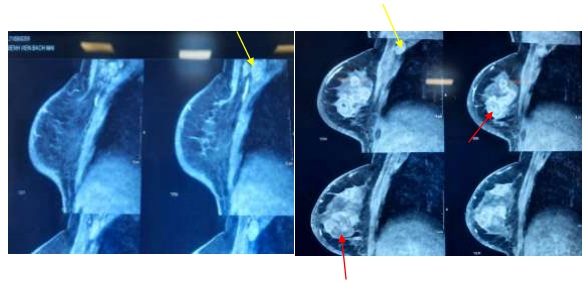

- Công hưởng từ tuyến vú: nhu mô vú phải vùng trung tâm và ½ trong có khối kích thước 33 x 53 mm, bờ không đều, tín hiệu không đồng nhất, ngấm thuốc không đồng nhất sau tiêm, chủ yếu ngoại vi. Tổn thương xâm lấn núm vú, thâm nhiễm xâm lấn da vú. Nhu mô còn lại ở ½ ngoài và ½ trên có nhiều khối kích thước lớn nhất 20 x 23mm, bờ không đều, một số vị trí tạo tua gai, ngấm thuốc mạnh không đồng nhất. Cơ ngực lớn và cơ gian sườn tăng tín hiệu T2FS, ngấm thuốc sau tiêm. Nhiều hạch nách phải mất cấu trúc rốn hạch lớn nhất 26 x 28mm.

Hình 3. Hình ảnh cộng hưởng từ vú

Tổn thương u vú đa ổ (mũi tên màu đỏ). Hạch nách phải (mũi tên màu vàng)